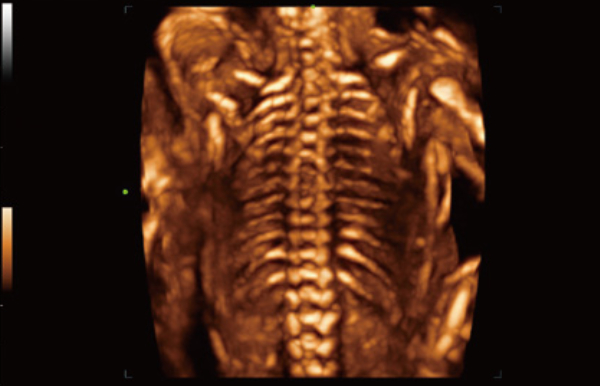

The Consona features new and concrete solutions, that efficiently help you to carry out smooth diagnoses for extensive type of patients.

No matter your routine is in hospitals, clinics, or you are honing skills in General Imaging applications, women's health care or cardiovascular specialties, you will find highly powerful tools available on this series to keep you stay ahead.

Comprehensive Imaging Solutions Powered by ZST+

The ZST+ platform is an extraordinary innovation, representing an ultrasound evolution. Transforming ultrasound metrics from conventional beam-forming to channel data based processing. It overcomes the traditional trade-off limitation among spatial resolution, temporal resolution and tissue uniformity, delivering exceptional image quality for infinite imaging solutions with non-stop improvements.